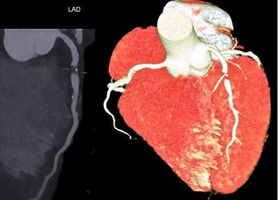

Kardiale CT bei einer 50-jährigen Patientin mit atypischen, nicht belastungsabhängigen Brustschmerzen.

CT-Angiographie (kontrastmittelgestützte Darstellung der Herzkranzgefäße): Ausschluss einer koronaren Herzerkrankung (vgl. Bilder; v. links: LAD; RCX; RCA)